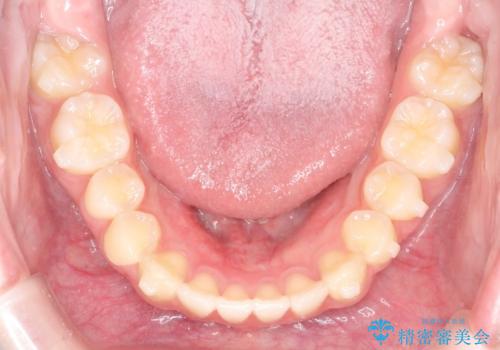

【インビザライン】前歯のガタガタをなおしたい

- 前歯のガタガタを主訴に来院されました。

開咬ぎみであったため、しっかりと前歯が噛むように計画を立てて治療をおこないました。

仕上がりも良く、患者様にも満足していただきました。

インビザラインは前歯を噛ませるような開咬の治療も得意としています。